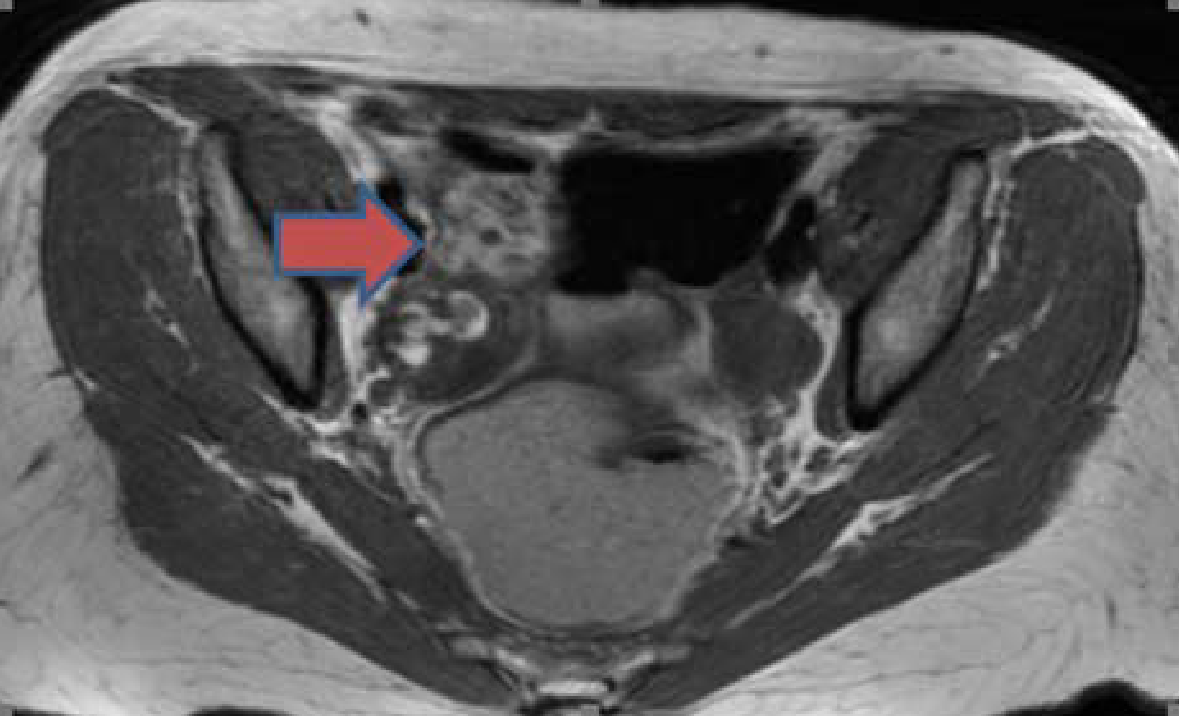

然而,患者血清抗NMDA受体抗体回报阳性。关键是,患者的盆腔超声及MRI提示右侧卵巢肿块,与囊性畸胎瘤表现一致。上述发现确认了抗NMDA受体脑炎的诊断。

图2 盆腔MRI发现右侧卵巢肿物,符合囊性畸胎瘤表现